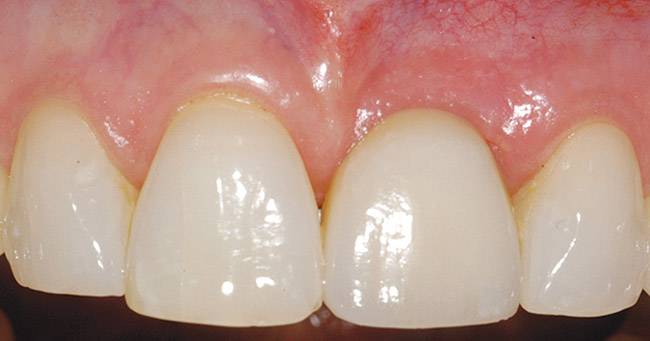

Treatment consisted of flapless extraction, socket grafting using mineralized bone allograft (Puros®, Zimmer Dental Inc, Carlsbad, CA), and a pedicled connective tissue graft36,37(Figure 11). Five months post-surgery, reentry was accomplished via a mid-crestal and labial sulcular incision. A crestal plasty was per- formed before implant placement into type II bone (Figure 12 and Figure 13). An immediate provisional was used for 3 months (Figure 14) before final crown fabrication (Figure 15).

Figure 14  Immediate provisional crown in place, 2 months after implant placement surgery. Please note gingival margin height of opposing lateral incisor (dotted line).

Figure 14

Figure 15  Completed crown. Note short distal papilla secondary to lack of appropriately placed point contact.

Figure 15